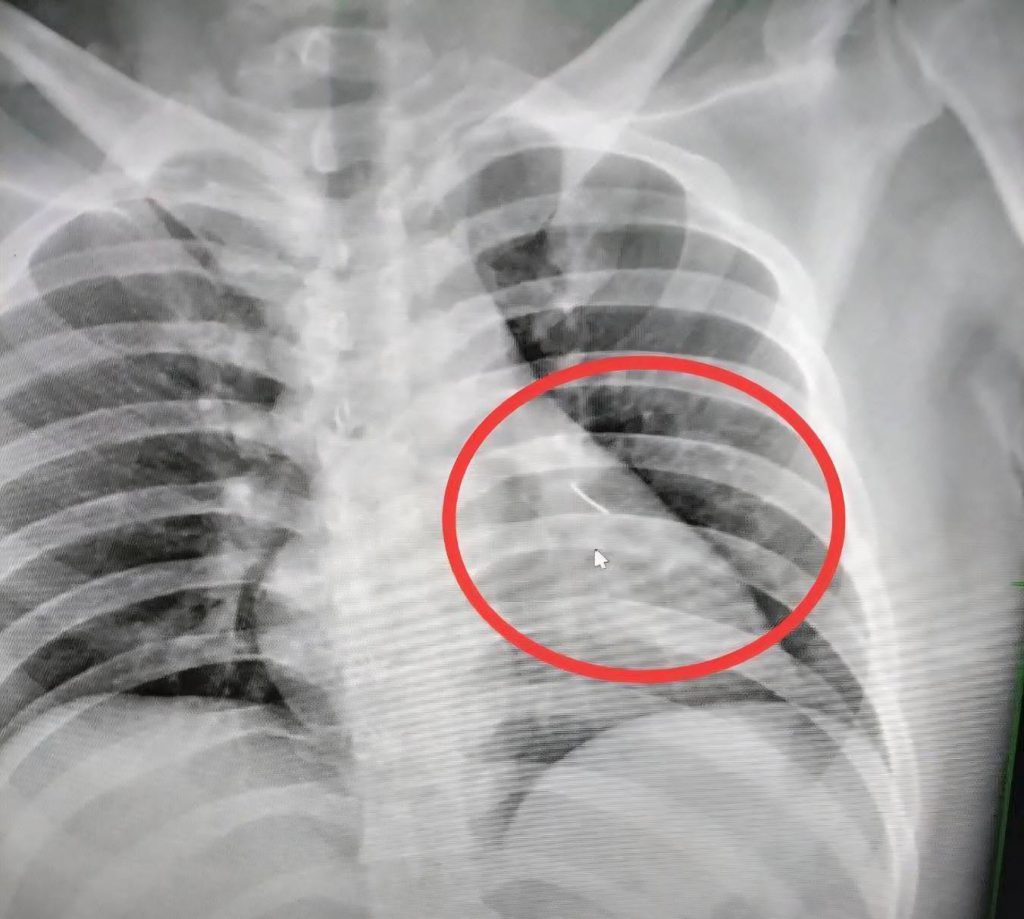

บุรีรัมย์ — เกิดเหตุไม่คาดคิด เมื่อชายวัย 27 ปีในพื้นที่อำเภอกระสัง ล้มตัวลงนอนพักผ่อนภายในบ้าน ก่อนเกิดอาการเจ็บหน้าอกอย่างรุนแรงโดยไม่ทราบสาเหตุ สุดท้ายแพทย์ตรวจพบ “เข็มเย็บผ้า” ยาวราว 7 เซนติเมตร ปักลึกบริเวณหน้าอกด้านซ้ายใกล้หัวใจ จนอาการเข้าขั้นสาหัส ต้องเร่งส่งต่อผ่าตัดด่วน

อย่างไรก็ตาม อาการผู้บาดเจ็บไม่ดีขึ้น แพทย์จึงส่งตรวจเอกซเรย์ ก่อนพบวัตถุแหลมคมฝังอยู่ภายในหน้าอกด้านซ้าย ใกล้หัวใจในจุดอันตราย จึงประสานส่งต่อไปยังโรงพยาบาลศูนย์บุรีรัมย์ เพื่อเข้ารับการผ่าตัดอย่างเร่งด่วน

ด้านญาติระบุว่า แพทย์แจ้งอาการอยู่ในขั้นสาหัส และให้ญาติลงนามยินยอมผ่าตัด เบื้องต้นคาดว่าเข็มเย็บผ้าอาจถูกลืมทิ้งไว้บนที่นอน และผู้บาดเจ็บที่อ่อนเพลียจากการทำงาน ได้ล้มตัวลงนอนจนถูกเข็มแทงเข้าไปบริเวณหน้าอก